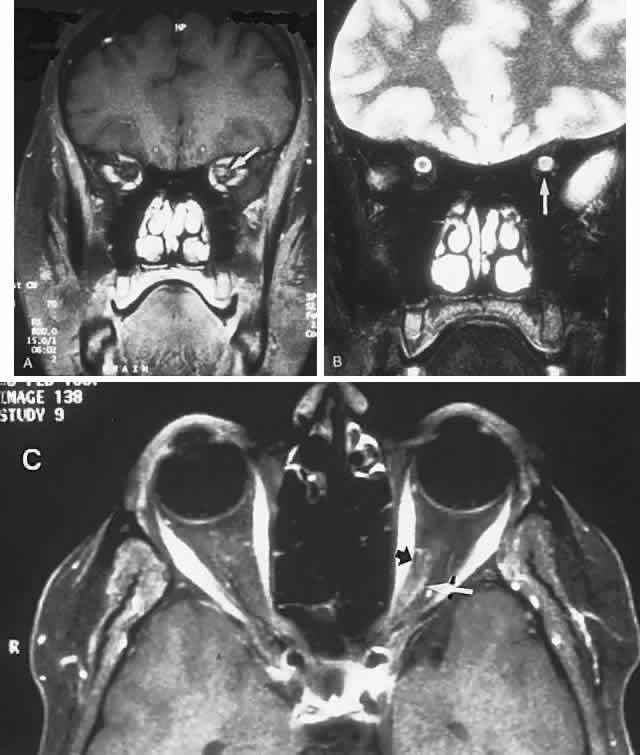

CONGENITAL HAMARTOMA SYNDROMES

The “neurophakomatoses” are a diverse group of disorders nosologically related by the presence of hamartomatous lesions, and, indeed, the term “hereditary hamartomatosis” is a more accurate description. However, whereas neurofibromatosis, tuberous sclerosis, and von Hippel-Lindau disease are transmitted with irregular dominance and considerable variation in penetrance, no hereditary basis of Sturge-Weber or angio-osteohypertrophy (Klippel-Trenaunay-Weber) syndrome has been established.

A hamartoma is a tumor of anomalous origin composed of elements normally present in the tissue in which it originates and with a limited capacity for proliferation. The following tumors may be classified as hamartomas: (1) in neurofibromatosis: optic gliomas (see Chapter 6), neurofibromas, and ganglioneuromas; (2) in tuberous sclerosis: retinal and cerebral astrocytomas, cutaneous angiofibromas (“adenoma sebaceum”), rhabdomyomas, and leiomyomas; (3) in von Hippel-Lindau disease: hemangioblastomas of the cerebellum and retina (including optic nerve head) and renal hypernephromas or cysts; (4) in Sturge-Weber disease: facial and choroidal cavernous hemangiomas and meningeal angiomatous malformations; and (5) in Klippel-Trenaunay-Weber syndrome: cutaneous nevi, visceral and limb hemangiomas, and orbitofacial venous varices.

If all disorders with neurocutaneous manifestations are considered, the term phakomatoses (Greek, phakos, “spot,” “birthmark”) is appropriate, and the catalog of “related” disorders becomes cumbersome. “The Phakomatoses,” Volume 14 of Vinken and Bruyn's Handbook of Clinical Neurology, is extraordinarily complete and serves as a source of detailed clinical descriptions of these diseases.146 Syndromes characterized by vascular hamartomas, that is, retinal-cerebellar angiomatosis (von Hippel-Lindau), and other angiomatous malformations, are discussed in Volume 2, Chapter 17.